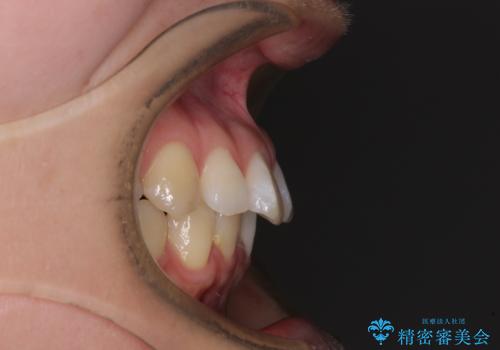

- 上顎前歯の隙間を気にして来院された患者様です。

下顎前歯が上顎前歯に食い込むような咬み合わせにより、上顎前歯が開いてしまっていたため、咬合高径の挙上により突き上げを改善するよう、インビザラインにより矯正治療を行うこととしました。